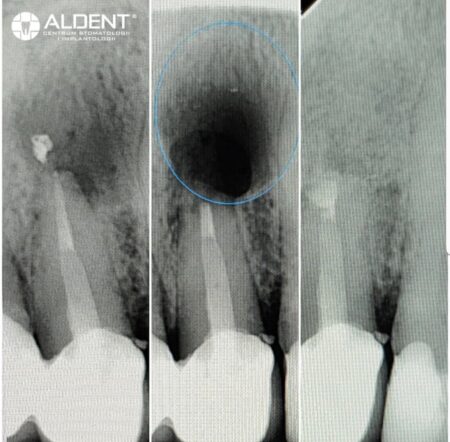

Resekcje wierzchołków korzeni zębów to skuteczna metoda leczenia stanów zapalnych w tkankach okołowierzchołkowych, które mogą wystąpić po nieprawidłowo przeprowadzonym leczeniu kanałowym. Ten zaawansowany zabieg chirurgiczny pomaga uratować ząb przed koniecznością ekstrakcji, eliminując źródło infekcji i przywracając zdrowie jamy ustnej.

Przebieg Zabiegu Resekcji

- Diagnostyka i Planowanie

- Przed przystąpieniem do zabiegu wykonujemy szczegółowe badania diagnostyczne, w tym zdjęcia rentgenowskie i tomografię komputerową, aby dokładnie ocenić stan korzenia zęba i otaczających tkanek.

- Usunięcie Zainfekowanej Tkanki i Resekcja Wierzchołka Korzenia

- Następnie chirurg usuwa zainfekowaną tkankę okołowierzchołkową i odcina wierzchołek korzenia zęba. Zabieg ten eliminuje źródło infekcji i zapobiega jej nawrotom.

- Uzupełnienie Ubytku Materiałem Kościozastępczym

- Ubytek po resekcji wypełniamy materiałem kościozastępczym, który wspomaga regenerację kości i przyspiesza proces gojenia.